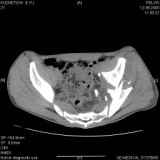

Уважаемые коллеги! Хотелось бы услышать совет по тактике лечения представлленого больного.

Поступил после лечения в одном изотделений области. Травма 2,5 месяца назад.

После выведения

из шока был произведен остеосинтез перелома бедра, предплечья, до перевода к нам проводилось

вытяжение по оси шейки бедра за стержень, введенный в большой вертел. На сегодня деформация

ригидна, клинически мобильности не определяется.